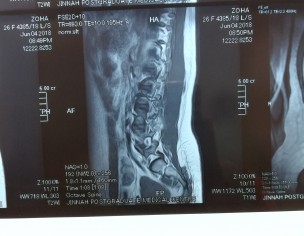

Attaching my MRI reports (MRI was in July). Everyone told me there is nothing serious just go for painkillers and physiotherapy. I was taking naproxen and was on physiotherapy from last 2 months. But still, there is no improvement. Sometimes I face severe back pain. So can someone please guide me what to do now? Please don't suggest me any treatment which is expensive as already invested a lot but all in vain. Is this disc herniation? Is it curable? I am seriously worried about it.